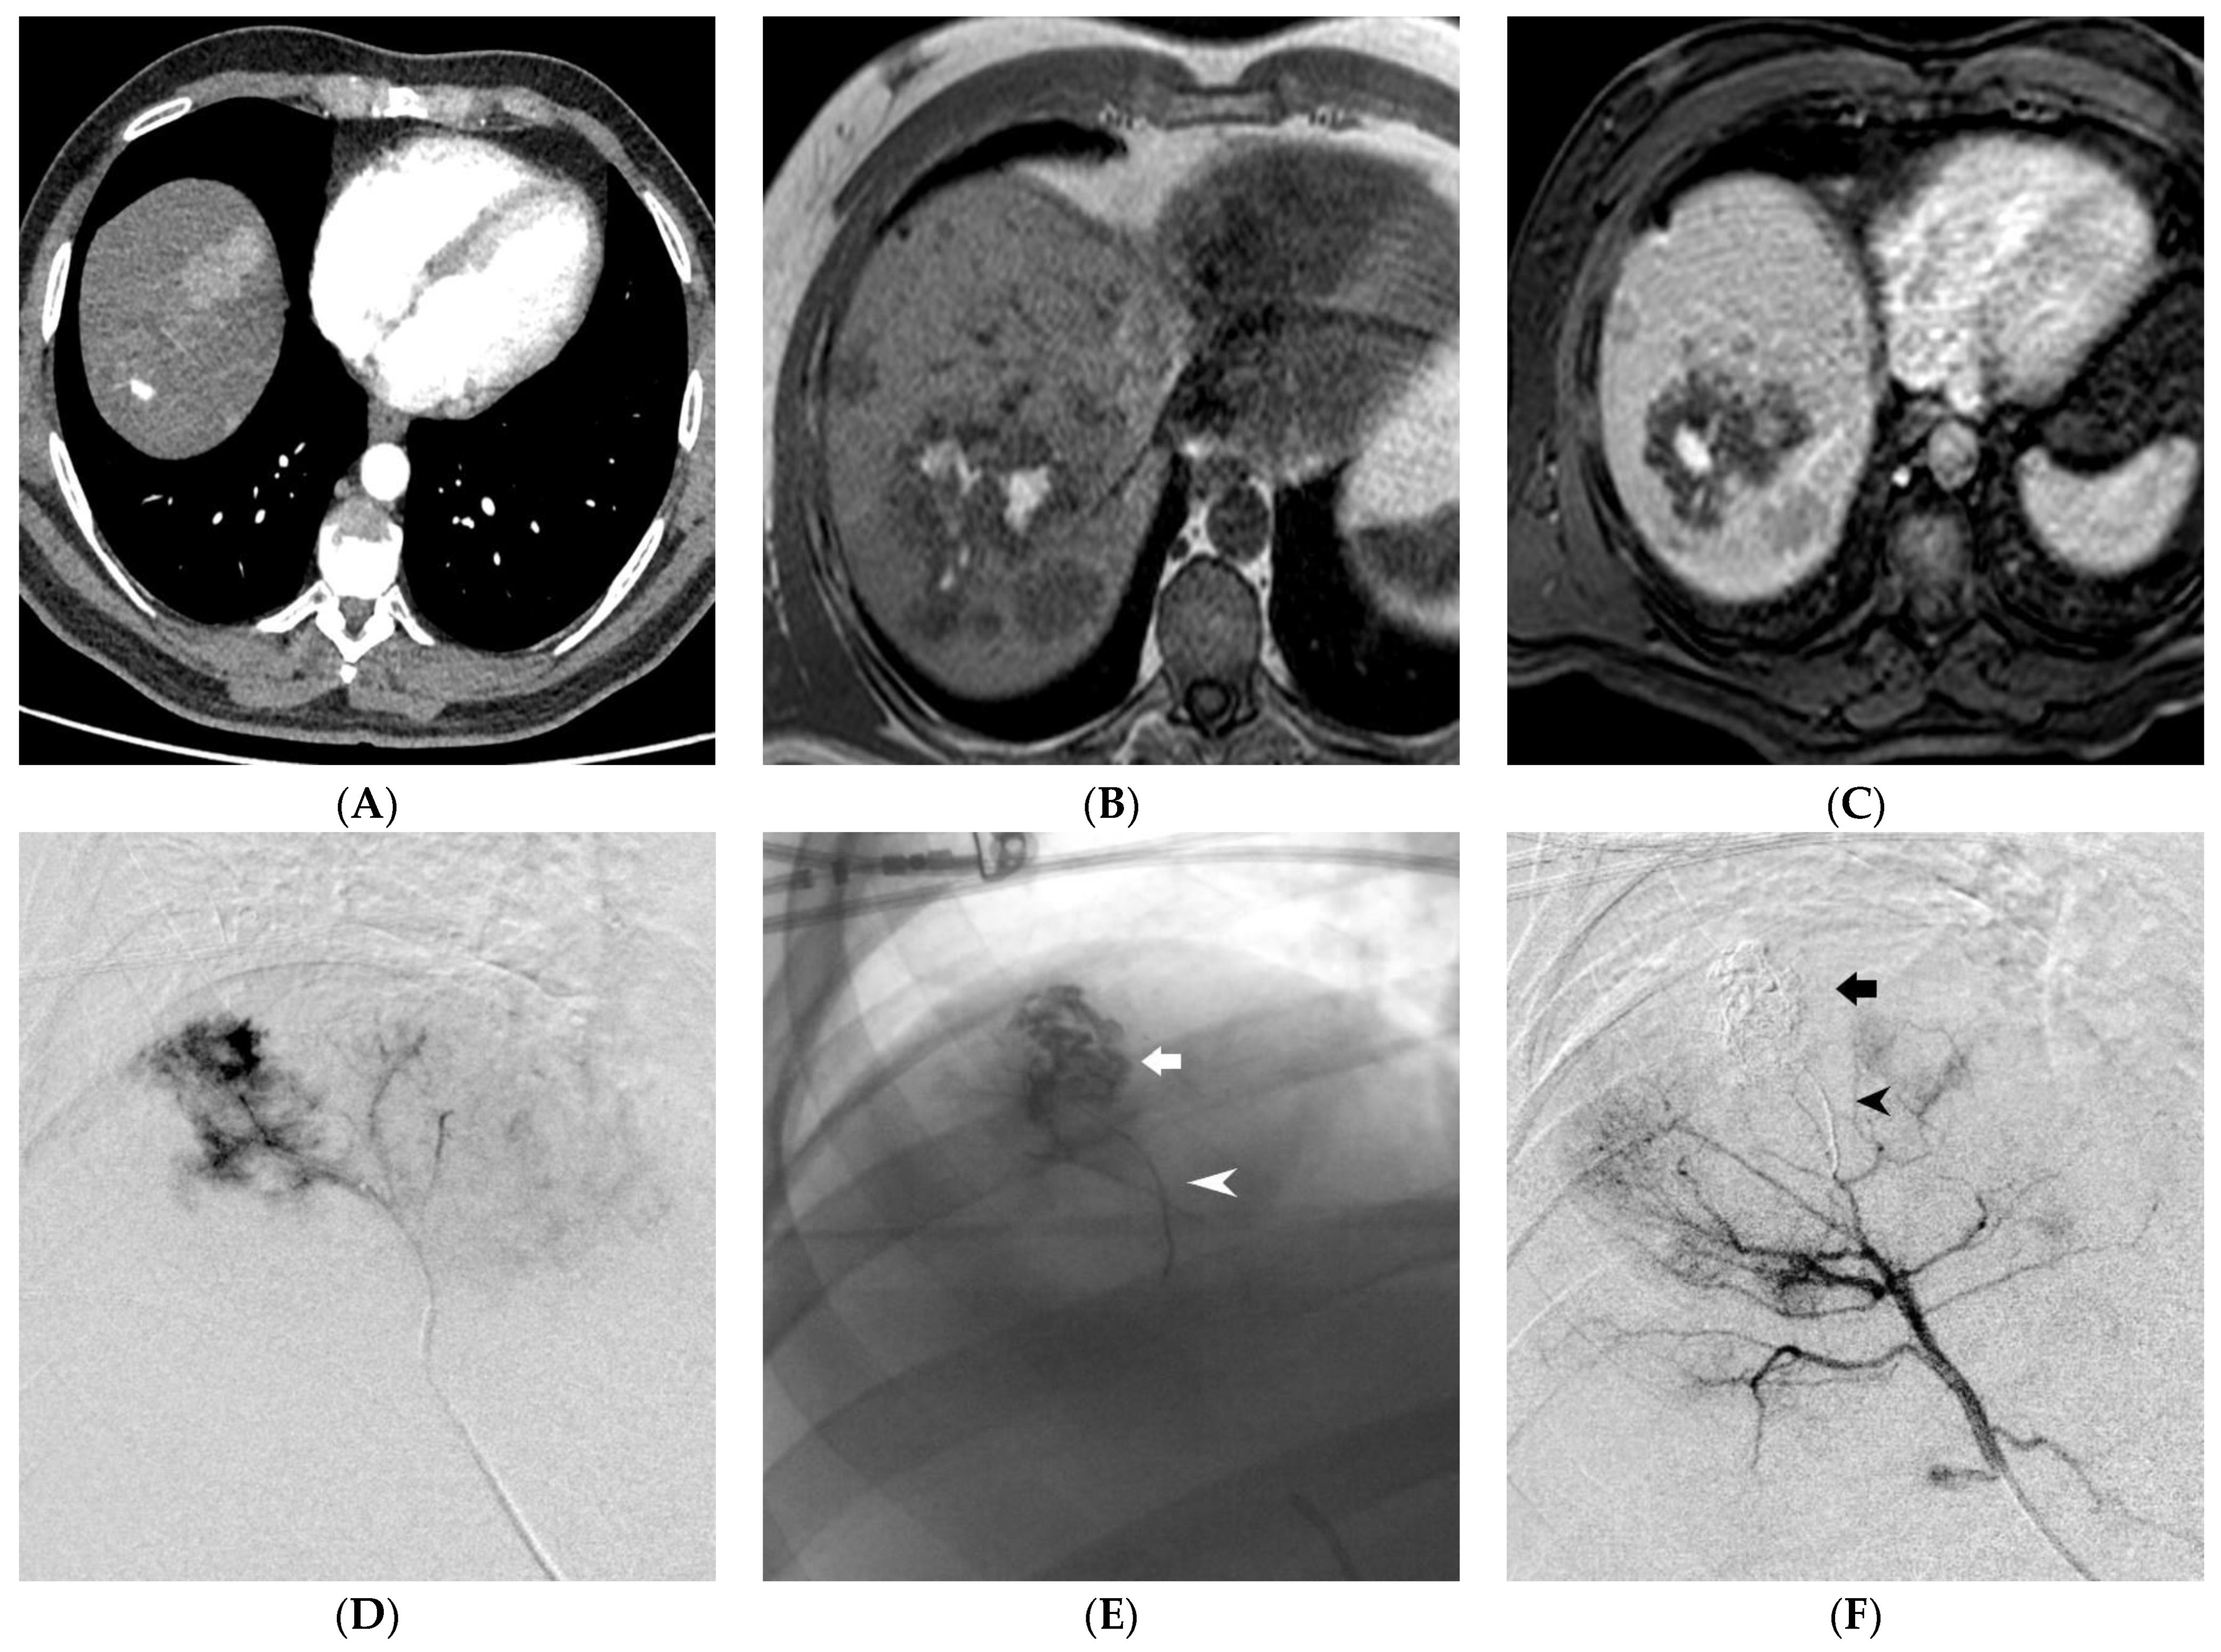

- Lucatelli, P.; Corona, M.; Teodoli, L.; Nardis, P.; Cannavale, A.; Rocco, B.; Trobiani, C.; Cipollari, S.; de Gyurgyokai, S.Z.; Bezzi, M.; et al. Use of Phil Embolic Agent for Bleeding in Non-Neurological Interventions. J. Clin. Med. 2021, 10, 701. [Google Scholar] [CrossRef]

- Né, R.; Chevallier, O.; Falvo, N.; Facy, O.; Berthod, P.-E.; Galland, C.; Gehin, S.; Midulla, M.; Loffroy, R. Embolization with ethylene vinyl alcohol copolymer (Onyx®) for peripheral hemostatic and non-hemostatic applications: A feasibility and safety study. Quant. Imaging Med. Surg. 2018, 8, 280–290. [Google Scholar] [CrossRef]

- Venturini, M.; Lanza, C.; Marra, P.; Colarieti, A.; Panzeri, M.; Augello, L.; Gusmini, S.; Salvioni, M.; De Cobelli, F.; Del Maschio, A. Transcatheter embolization with Squid, combined with other embolic agents or alone, in different abdominal diseases: A single-center experience in 30 patients. CVIR Endovasc. 2019, 2, 1–13. [Google Scholar] [CrossRef]

- Fontana, F.; Piacentino, F.; Ossola, C.; Coppola, A.; Curti, M.; Macchi, E.; De Marchi, G.; Floridi, C.; Ierardi, A.M.; Carrafiello, G.; et al. Transcatheter Arterial Embolization in Acute Non-Variceal Gastrointestinal Bleedings: A Ten-Year Single-Center Experience in 91 Patients and Review of the Literature. J. Clin. Med. 2021, 10, 4979. [Google Scholar] [CrossRef]

- Tipaldi, M.A.; Orgera, G.; Krokidis, M.; Rebonato, A.; Maiettini, D.; Vagnarelli, S.; Ambrogi, C.; Rossi, M. Trans Arterial Embolization of Non-variceal Upper Gastrointestinal Bleeding: Is the Use of Ethylene–Vinyl Alcohol Copolymer as Safe as Coils? Cardiovasc. Interv. Radiol. 2018, 41, 1340–1345. [Google Scholar] [CrossRef] [PubMed]